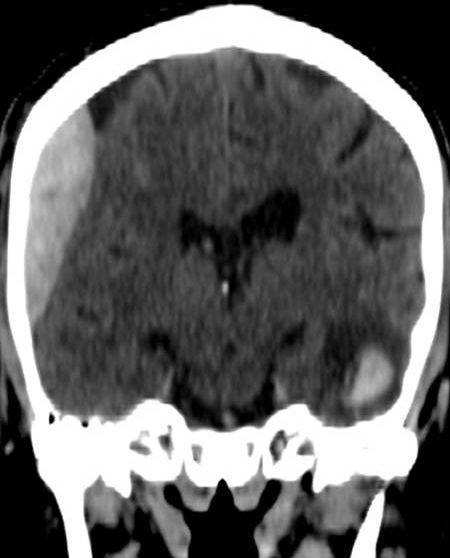

• Contusion hemorrhage occurs upon sudden deceleration (e.g. car accident - collision) when the brain parenchyma due to its inertness keeps moving and hits the cranial bone. Frequently, contusion develops on the opposite side as well, since on an abrupt stop the brain collides with the bone than bounces off and hits the opposite wall of the skull. (coup - contrecoup effect)

7. Elderly female was suffered a direct hit in the parietal region. Coronal reconstruction of a unenhanced CT scan: At the site of the impact on the right side parietally a typical lens shaped epidural hematome is formed. On the opposite side in the temporal lobe at the contrecoup contusion site parenchymal bleeding is seen